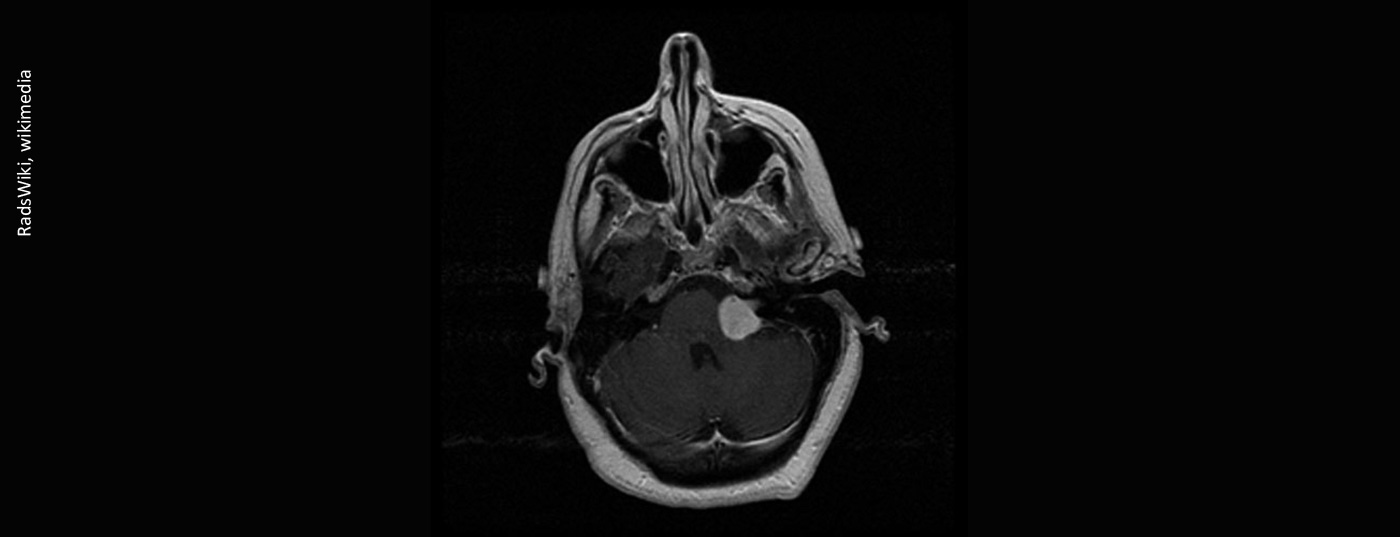

vestibular-schwannoma-003

• Akustikusneurinom

Schwindel und Schwerhörigkeit – vom Symptom zur Diagnose

Das Akustikusneurinom (Schwannom, Neurilemmom) zählt zu den häufigsten gutartigen Tumoren (WHO Grad I) der Hirnnerven. Der Name hat sich im deutschen Sprachraum für den Tumorbefall des Nervus vestibulocochlearis etabliert. Neben dem Neurinom des VIII. Hirnnerven kommen diese Raumforderungen auch am N. trigeminus und facialis, jedoch signifikant geringer, vor.